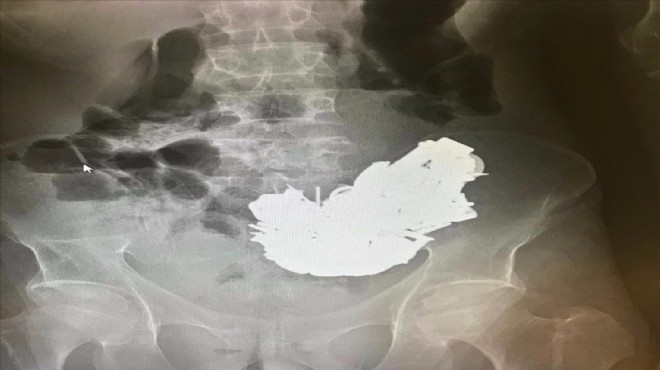

Bornova ilçesinde yaşayan 41 yaşındaki E.D, geçen hafta aniden rahatsızlanınca ailesi tarafından Ege Üniversitesi (EÜ) Tıp Fakültesi Hastanesi Acil Servisi'ne götürüldü. Doktorlar, röntgen filminde midede çok sayıda cisim bulunduğunu tespit etti.

Sağlık durumu kötüleşen hasta için acil ameliyat kararı verildi. Hastanın midesindeki farklı boyutlarda ve toplam 580 gram ağırlığında yaklaşık 200 cisim, 3 saat süren ameliyatla alındı. Hastanın midesinden çıkarılan cisimler arasında bulunan mıknatıs, anahtar, boş kovan, çivi, cıvata, anahtarlık, madeni para, metal harfler ve çeşitli boyuttaki metaller, sağlık personelini şaşırttı.

Midedeki metallerin mıknatıs sayesinde bir arada toplanması, röntgen görüntüsüne de yansıdı.